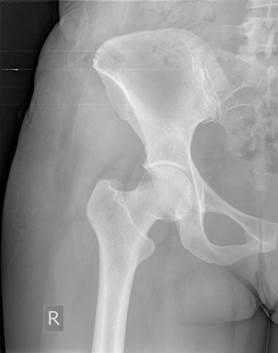

На контрольных рентгенограммах донорских зон нарушения контура гребня выявлено не было, что свидетельствует о правильности выполнения вмешательства и об эффективности разработанного устройства (рис. 4).

Рис. 4. Рентгенограмма правой половины таза после взятия костного трансплантата из крыла подвздошной кости при помощи нового устройства (внешний контур гребня сохранен)